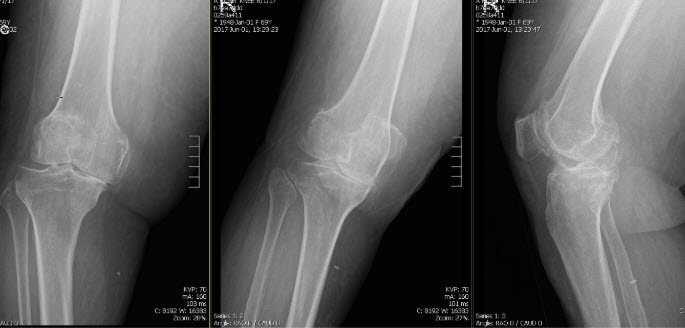

La paciente es una mujer de 75 años que presenta dolor bilateral en la rodilla. Había empeorado sustancialmente el dolor en la rodilla derecha de forma progresiva durante los últimos 6 años. El dolor ha impedido al paciente realizar actividades de la vida diaria,...